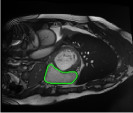

From the above discussions, we have discovered the significant potential of applying Retinex theory to image segmentation and explored its fundamental differences from traditional models. Traditional image segmentation models typically focus on the impact of intensity information on the segmentation results. Therefore, when faced with complex segmentation scenarios, the segmentation results are often affected by lighting, artifacts, and unclear boundaries in the image. As shown in Fig. 1, we present the results of the classical local model LIF [ZHANG20101199] for segmenting brain tumor images along with surrounding tissue edema. The irregular ring-like enhancement caused by the edematous tissue leads to irregular boundaries and low contrast in the images. Consequently, the LIF model can only identify the central necrotic and liquefied regions of the tumor, failing to detect the boundaries and becoming trapped in local minima. In this paper, we draw inspiration from the Retinex theory, which is widely applied in the field of image enhancement. According to Retinex theory, the reflectance component characterizes the intrinsic structural properties of the observed image and preserves texture information independent of illumination variations. By integrating this reflectance component into the level set framework, our model achieves robust segmentation of medical images even under severe intensity inhomogeneity. In addition, a linearized Structural-Prior is proposed to restore intensity consistency and capture local geometric features, thereby improving boundary localization in complex or blurred regions. Furthermore, a relaxed binary level set representation is employed to enhance robustness against noise and to enable accurate tracking of complex contours. Based on these innovations, we propose a novel variational reflectance-based level set model (RefLSM) that simultaneously corrects bias fields and performs segmentation. Experimental results demonstrate that RefLSM significantly outperforms conventional level set methods in both segmentation accuracy and robustness. We present the results of our model segmenting the two brain tumor images mentioned above in Fig. 2.

To address the challenge of segmenting images with severe intensity inhomogeneity, we propose a linearized structural prior that directly operates on the reflectance component . Reflectance-based structural information is more robust to illumination variations and bias field distortions, helping preserve weak edges and subtle anatomical boundaries. As shown in Fig. 2, our method can accurately delineate tumor boundaries and surrounding edema even under severe inhomogeneity, where traditional intensity-based models often fail. The proposed prior aligns smoothed reflectance gradients with data-driven directions, enhancing inter-region contrast, preserving weak edges, and stabilizing the evolution of . Formally, we define the linear structure operator as the gradient field of the smoothed reflectance: